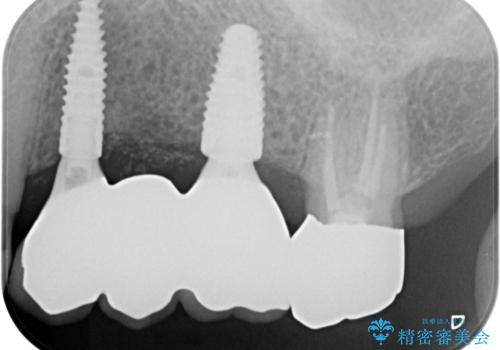

しっかりとまた物を噛めるようになるために、インプラントを用いて咬合機能を回復していきます。

- 106.7万円(インプラント×2・チタンカスタムアバットメント×2・ジルコニアクラウン×3・仮歯×3)費用は治療当時の料金となります

入れ歯とは比べものにならないくらいしっかりと噛めるようになり、大変喜んでいただくことができました。